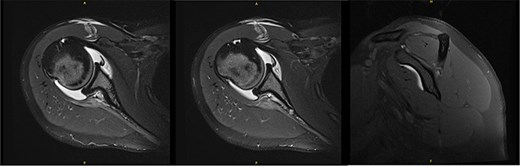

Ten years after initial presentation, the patient returned with increased right shoulder pain after overhead injury at the gym. Her exam included a positive O’Brien’s test, and external rotation weakness. Interval EMG was normal; MRI demonstrated mild supraspinatus tendinosis, and infraspinatus atrophy with unchanged fatty infiltration (Fig. 6). The patient’s pain was hypothesized to be due to infraspinatus atrophy and overuse of other rotator cuff musculature. She elected to manage her symptoms with self-directed therapy.

MRI at final follow-up demonstrated mild supraspinatus tendinosis, and infraspinatus atrophy with continued significant fatty infiltration, unchanged from prior imaging.